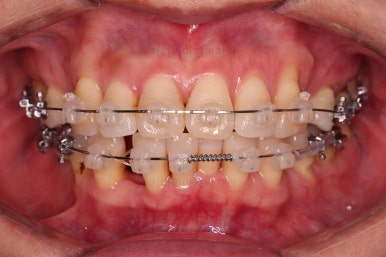

장치를 부착했습니다.

이번 환자분이 선택한 장치는 데이몬 클리어라고 하는 현존하는 자가결찰 세라믹 장치 중에 가장 심미적인 장치입니다.

사실상 멀리서 보면 철사를 제외하고는 거의 눈에 띄지 않는 모습인데요.

단점은 부피가 다른 장치들보다 약간은 더 크기 때문에 입이 약간 더 나와보일 수 있다는 점이죠.

작은 어금니를 발치하고 치열을 가지런하게 해줍니다.

아직 아래 앞니에 있는 유치는 발치하지 않았는데요.

현 상태로 발치를 하게 되면 기구 접근이 되지 않아 광범위하게 뼈를 갈아내며 뽑아야 됩니다.

교정을 하면 기구 접근이 충분히 되도록 공간을 벌린 뒤 발치를 할 수 있어 기간은 더 걸릴 수 있겠지만 잇몸뼈를 보존하고 수월하게 발치를 하려면 교정만한게 또 없죠.